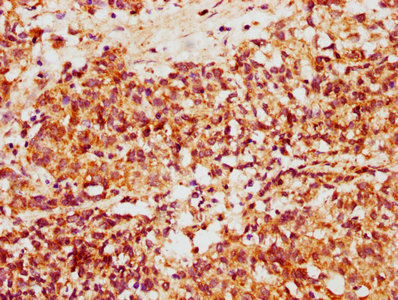

IHC image of CSB-PA884463LA01HU diluted at 1:500 and staining in paraffin-embedded human ovarian cancer performed on a Leica BondTM system. After dewaxing and hydration, antigen retrieval was mediated by high pressure in a citrate buffer (pH 6.0). Section was blocked with 10% normal goat serum 30min at RT. Then primary antibody (1% BSA) was incubated at 4°C overnight. The primary is detected by a biotinylated secondary antibody and visualized using an HRP conjugated SP system.